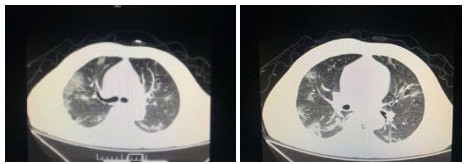

| 图 4 患者,男性,59岁,湖北籍,春节回乡探亲返沪,发热2 d入院,体温37.8℃, 乏力,既往体健。血白细胞总数及淋巴计数正常,甲型、乙型流感筛查阴性,新型冠状病毒核酸检测阳性。肺部CT提示双肺多发磨玻璃结节,病灶贴近胸膜伴支气管充气征及血管充血、增粗,可见部分纤维条索影 Fig 4 Case 4, male, 59 years old, born in Hubei Province, returned to Shanghai during the Spring Festival. He was hospitalized 2 days after fever, with a body temperature of 37.8℃ with fatigue. Normal WBC and lymphoid count, negative influenza A and B virus screening, positive novel coronavirus nucleic acid test. Lung CT showed multiple ground glass nodules in both lungs. The focus was close to the pleura, accompanied by bronchiectasis, hyperemia and thickening of blood vessels. Some fibrous bands could be seen |

| 图 5 患者,女性,44岁,沪籍,发病前10 d内有与确诊NCP患者接触史。出现发热,体温38.5℃,乏力,伴肌肉酸痛,既往体健。血白细胞总数及淋巴计数正常,甲型、乙型流感筛查阴性,新型冠状病毒核酸检测阳性。肺部CT提示双肺多发磨玻璃结节,病灶贴近胸膜伴支气管充气征及病变内血管充血、增粗 Fig 5 Case 5, female, 44 years old, born in Shanghai, had contact history with NCP patients within 10 days before the onset of the disease. Her body temperature was 38.5℃, with fatigue, muscle ache, previous physical fitness. Normal WBC and lymphoid count, negative influenza A and B virus screening, and positive novel coronavirus nucleic acid test. Lung CT showed multiple ground glass nodules in both lungs. The lesions were close to the pleura with bronchiectasis and congestion and thickening of blood vessels in the lesions |